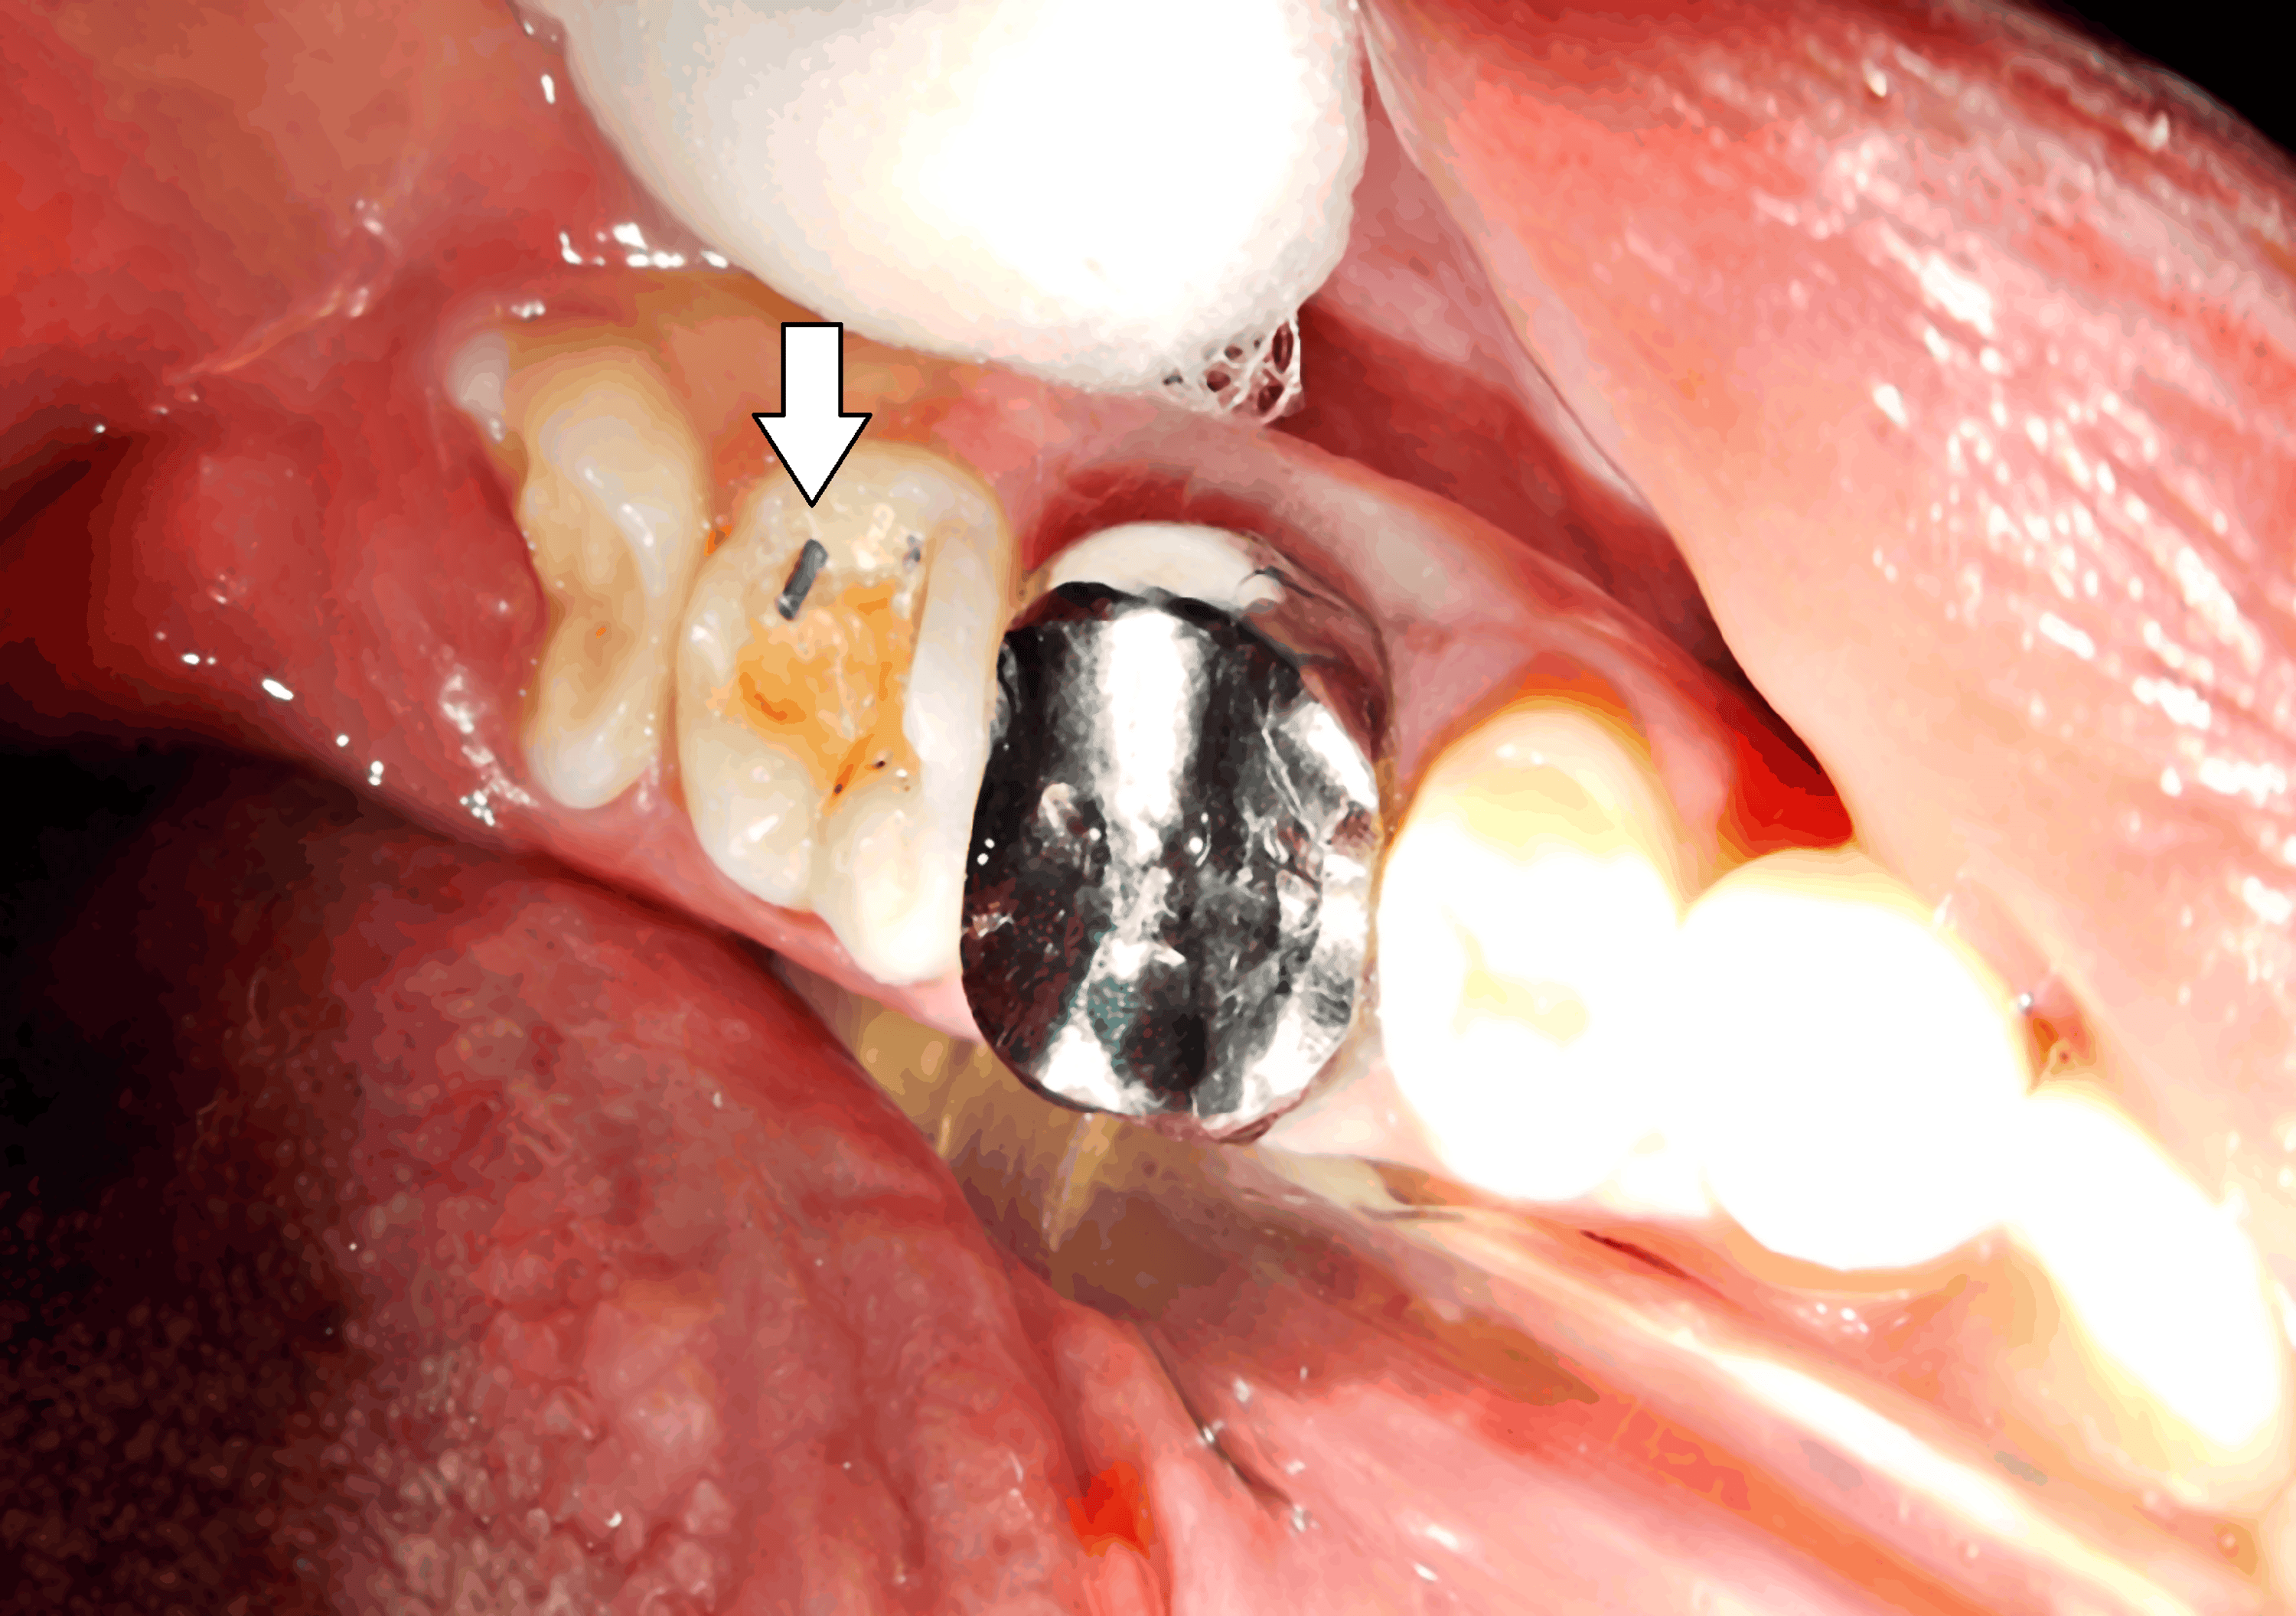

From www.cureus.com

PinRetained Amalgam An Intricate Restorative Case Study Cureus Pin Retained Amalgam — a pin retained restoration is an intricate restoration involving the insertion of one or more pins into the dentin to provide. a pin retained restoration is an intricate restoration involving the insertion of one or more pins into the dentin to provide. the authors compared the clinical performance of complex amalgam restorations, replacing at. a. Pin Retained Amalgam.